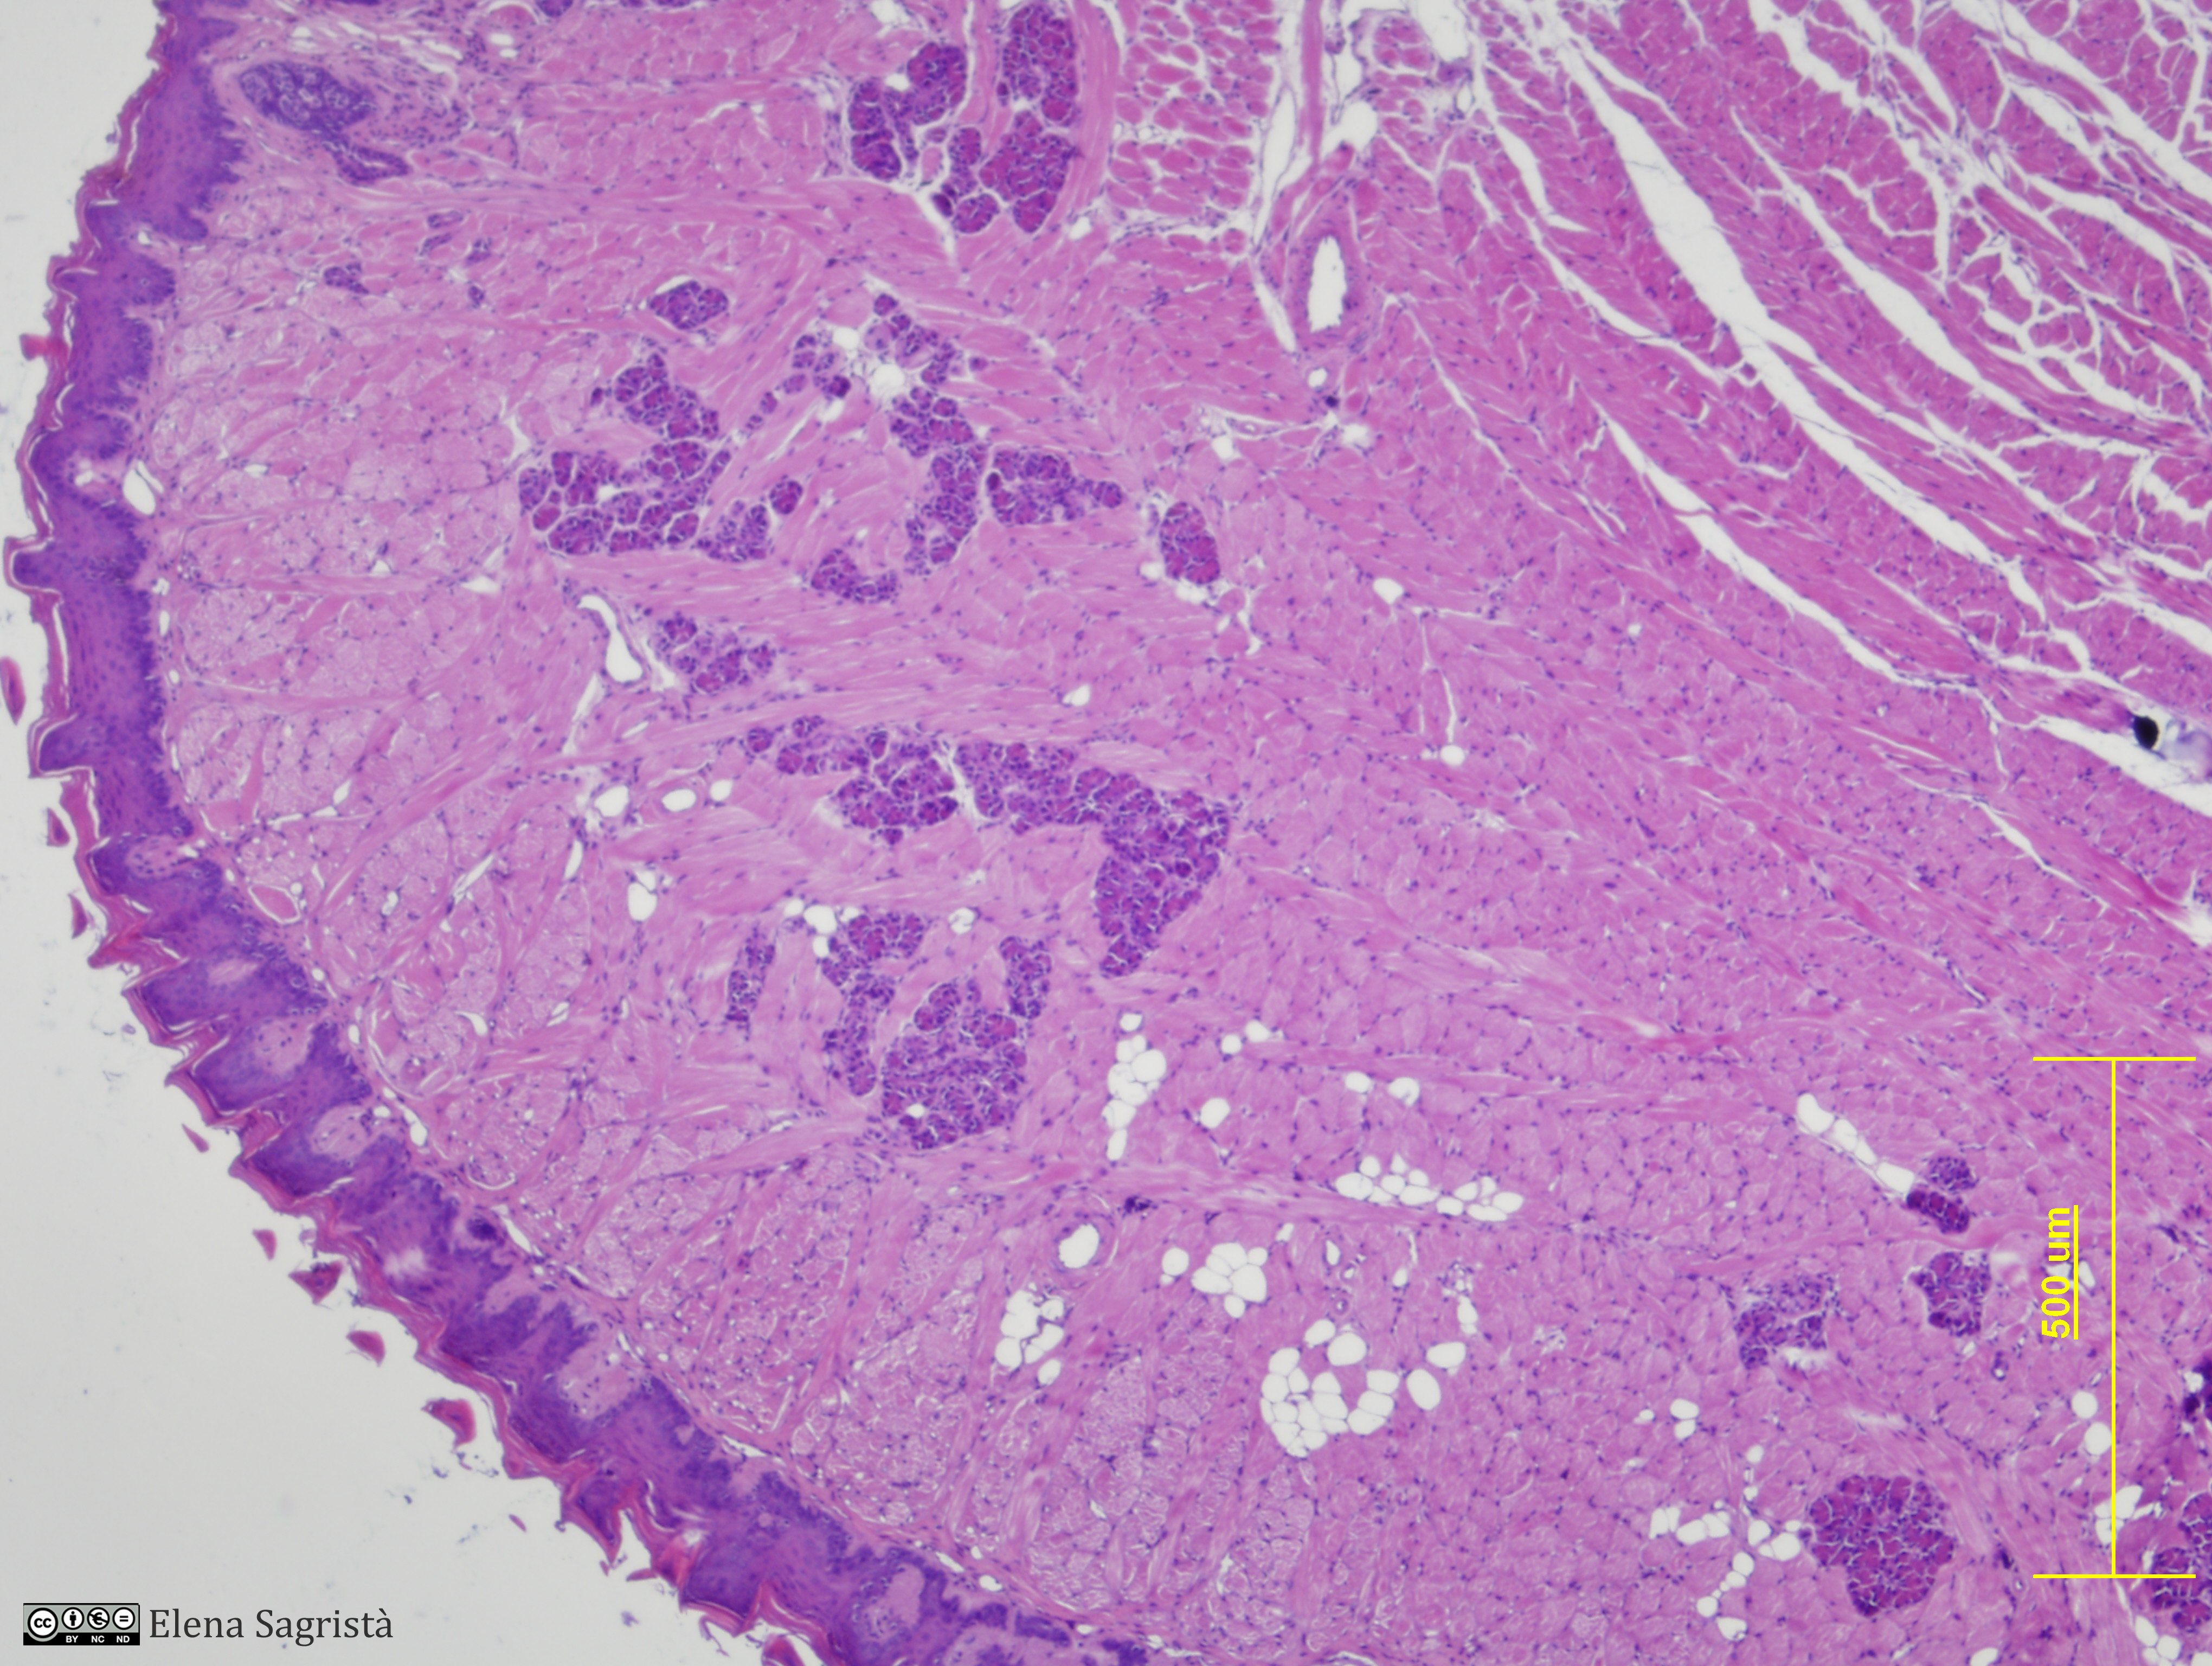

Histologia imatges: 14 Llengua

Imatges de preparacions histològiques de Llengua. Microscopia òptica.